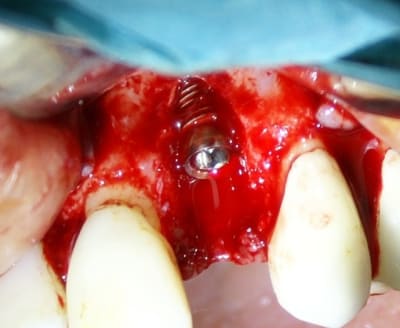

Tout à fait d'accord growler et c'est d'ailleurs ce que l'on peut voir sur le cas suivant. Fracture radiculaire, aucune infection periradicualire. Extraction et implantation immediate. Espace existant entre l'implant et l'alvéole est comblé par du BioOss. Un logement sous gingival est formé en vestibulaire et palatin de facon à pouvoir recouvrir le tout par BioGide et un conjonctif enfoui.

L'implant est de 15mm mais l'alvéole était large et 50% environ de la surface implantaire n'était en contact qu'avec du BioOss. J'ai pour cela préféré enfouir.

Petite question dentiste 57 : il semblerait dans le 2eme cas que tu présentes que tu ne recouvres pas ton implant par la membrane (qui pourrait comme l'a dit Amibien être poinconnée pour laisser passer ton pilier). Si c'est bien le cas peux tu m'expliquer pourquoi ? Quel est le risque à ton sens que ton comblement palatin et vestibulaire se fasse la malle par le "sulcus" entourant ton implant ?

Bien vu! cela demande une petite explication.

j'ai d'abord enfoui le plus apicalement possible ma membrane car je devais en premier lieu combler avec le moignon en place de manière à ne pas mettre de substitut osseux dans l'hexagone interne. Une fois mon substitut en place je travail le porte implant qui sert de support à la provisoire, il y a donc montages et démontages successifs.

Comme tu l'as si bien remarqué, j'ai laissé une minuscule languette de membrane, je l'a tracte très légèrement (une fois seulement la provisoire validée et prête à poser) et la fixe en la transperçant avec le moignon portant la provisoire. ainsi je recouvre bien le substitut osseux en palatin et en vestibulaire également.